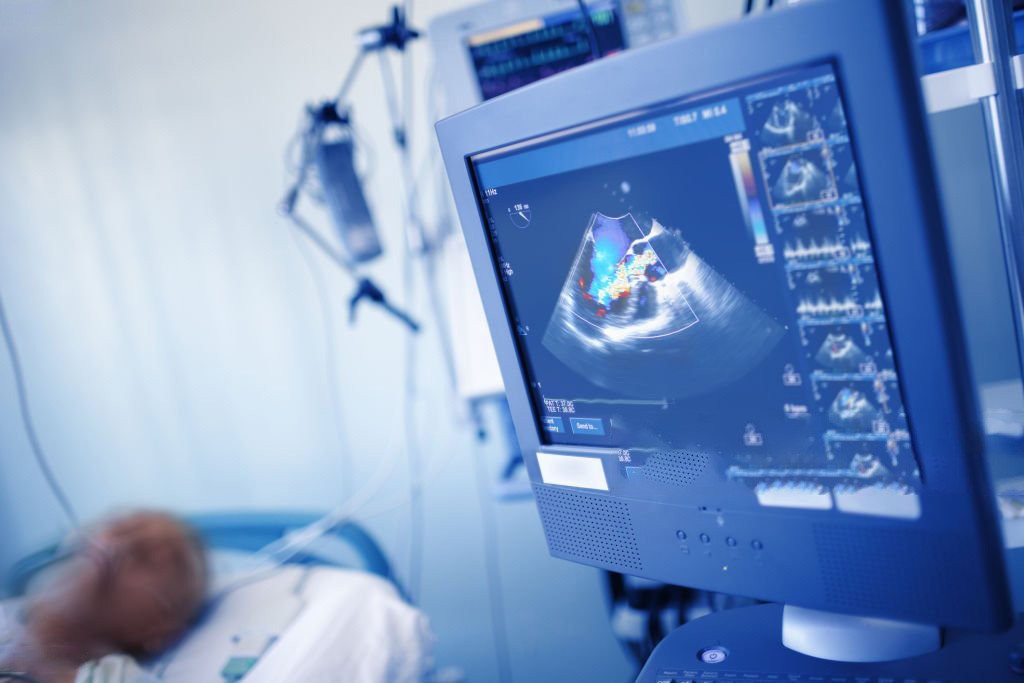

Echo serca, czyli echokardiografia, to nieinwazyjne badanie obrazowe wykorzystujące ultradźwięki do oceny budowy i pracy serca. Pozwala ocenić wielkość jam serca, kurczliwość mięśnia sercowego, funkcję zastawek oraz przepływ krwi przez serce.

Badanie jest bezbolesne i nie wymaga specjalnego przygotowania. Pacjent leży na leżance, a lekarz przykłada do klatki piersiowej głowicę ultrasonograficzną, która pozwala uzyskać obraz serca na monitorze. Całość trwa zazwyczaj od kilkunastu do kilkudziesięciu minut.